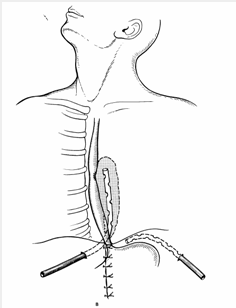

Kəskin mediastinit şübhəsi olan xəstə təcili xəstəxanaya yatırılır, diaqnoz qoyulan kimi aktiv dəstək, antibiotikoterapiya başlanılır və cərrahi müalicə həyata keçirilir. Kəskin mediastinitin müalicəsində cərrahi müalicə əsas tədbirdir və iki məqsədlə yerinə yetirilir: irinliyin sanasiyası-drenajı və səbəbin aradan qaldırılması (Şəkil 12).

Şəkil 12. Divararalığının drenajı

Sanasiya-drenaj üçün divararalığına yuxarıdan, transsternal, transtorakal yollarla müdaxilə etmək olar. Səbəbi aradan qaldırmaq üçün edilən əməliyyatlar səbəbdən asılı olaraq dəyişir.

- Qida borusu perforasiyalarında ezofaqusda xəstəliyin olub-olmamasından, perforasiyanın yeri və ya müddətindən asılı olaraq müalicələr seçilir: perforasiyanı tikmə, rezeksiya, diversiya, stend, drenaj (Şəkil 13).

Şəkil 13. Qida borusu perforasiyasında müalicə prinsipləri